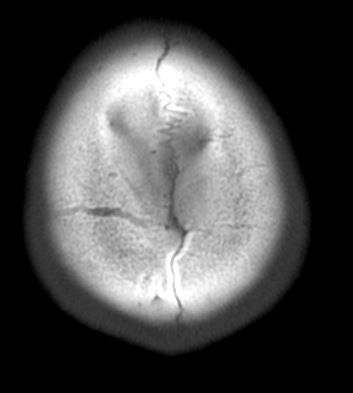

• 2번 째 사진